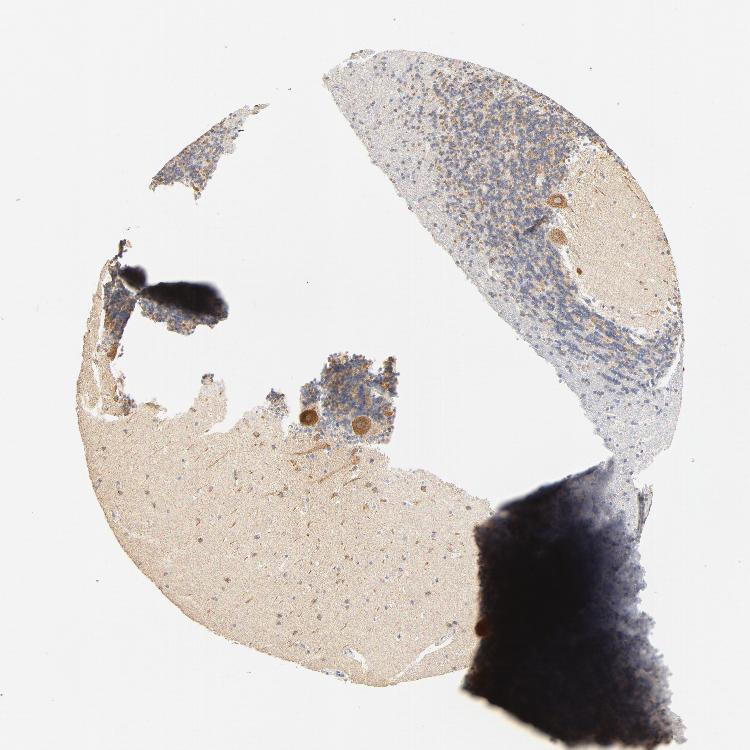

CEREBELLUM - Antibody stainingi

Antibody staining in the annotated cell types in the current human tissue is reported as not detected, low, medium, or high, based on conventional immunohistochemistry profiling in selected tissues. This score is based on the combination of the staining intensity and fraction of stained cells.

Each image is clickable and will lead to virtual microscopy that enables deeper exploration of all samples and also displays staining intensity scores, fraction scores and subcellular localization as well as patient and tissue information for each sample.

Antibody HPA002485Antibody CAB004080

Purkinje cells HighHigh

Cells in granular layer MediumLow

Cells in molecular layer MediumLow